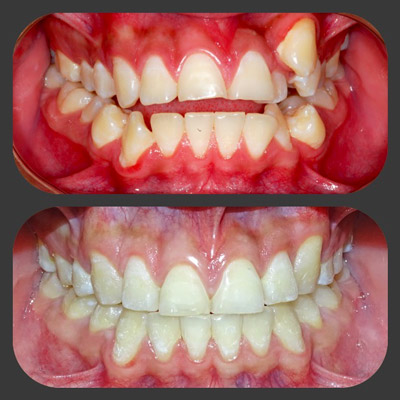

img

La paciente llega a la consulta por una úlcera en el labio. Cuando la revisamos, y nos dimos cuenta que era un problema por una mala posición, ejecutamos todo con una buena planeación y obtuvimos resultados excelentes.